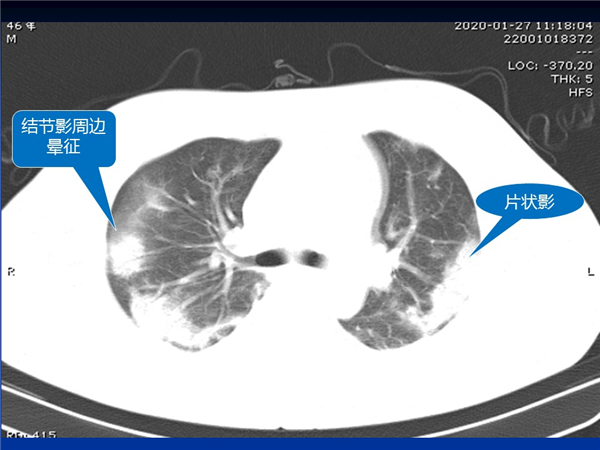

【病例分享】新型冠狀病毒感染肺部CT影像4例(常德市第一人民醫(yī)院)